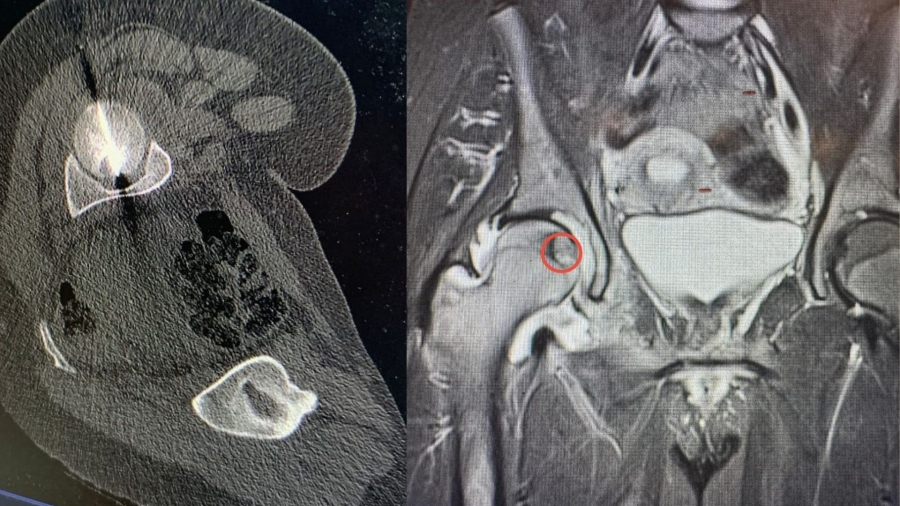

• طب و صحة